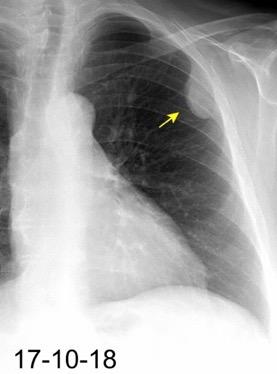

Neumonía a neumococos base izda. con derrame que aumenta.

Broncograma en lateral y en US.

(36-66% en ingresados)